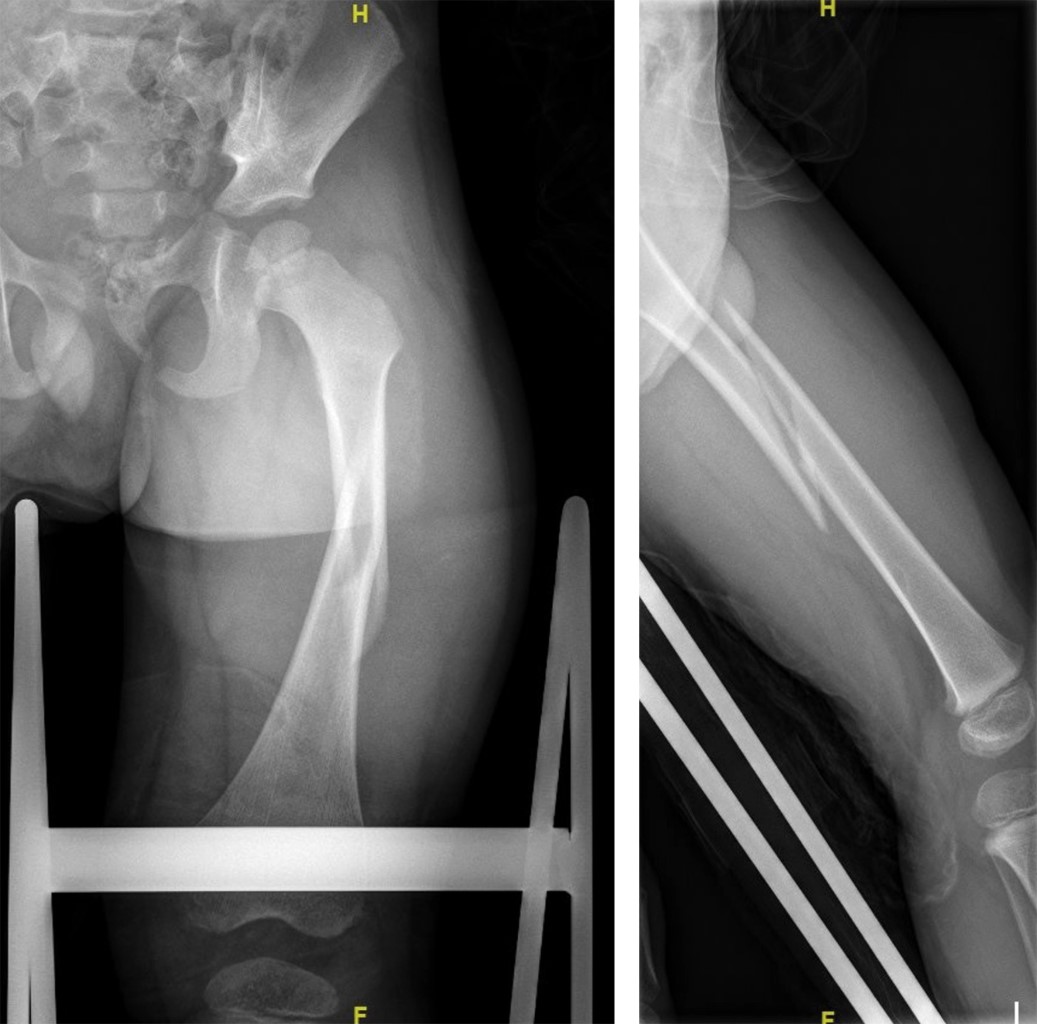

Figure 3